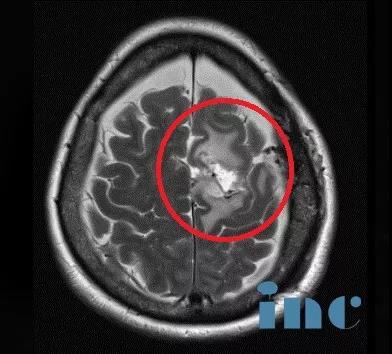

臨床診斷:左側(cè)額部大腦鐮旁腦膜瘤。

術(shù)前影像資料:左側(cè)大腦鐮旁巨大腦膜瘤,鈣化和瘤周壓迫、水腫效應(yīng)明顯。